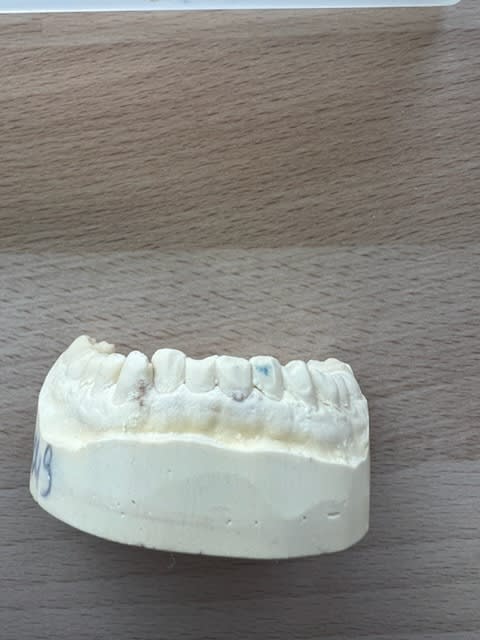

Le modèle du bas!

Désolé du retard chers collègues!